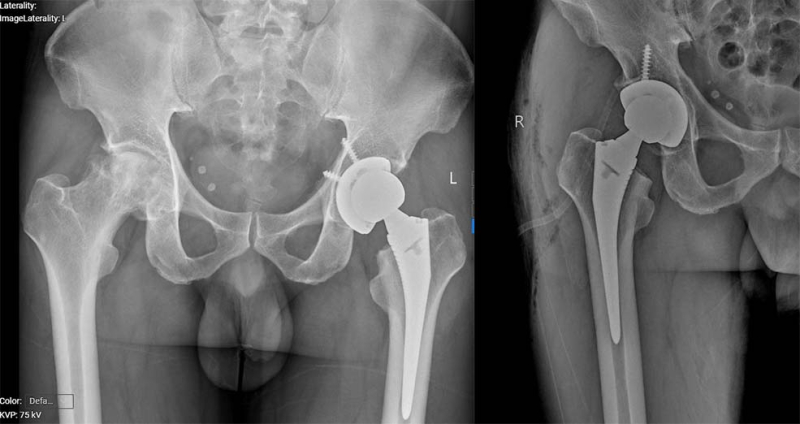

Mới đây, các bác sĩ Khoa Chấn thương Chỉnh hình, Bệnh viện Bãi Cháy đã phẫu thuật thay khớp háng cho bệnh nhân VŨ KIM H (40 tuổi, ở phường Móng Cái, tỉnh Quảng Ninh). Bệnh nhân có tiền sử hoại tử chỏm khớp háng hai bên, đã được phẫu thuật thay khớp háng trái cách đây 1 năm. Gần đây bệnh nhân xuất hiện đau và hạn chế vận động khớp háng phải. Kết quả chụp xquang có hình ảnh đặc xương kèm tiêu xương không đều vùng chỏm xương đùi phải gây biến dạng xương đùi và hẹp không đều khe khớp háng phải. Các bác sĩ đã hội chẩn và đánh giá tình trạng hoại tử vô khuẩn chỏm xương đùi phải tiến triển và không còn khả năng bảo tồn. Người bệnh được chỉ định phẫu thuật thay toàn bộ khớp háng háng phải.

Hình ảnh khớp phải trước và sau phẫu thuật

Ca phẫu thuật do BSCKII Vũ Quang Nghĩa – Trưởng Khoa Chấn thương chỉnh hình Bệnh viện Bãi Cháy thực hiện đã thành cắt bỏ tổn thương hoại tử, thay khớp háng bằng vật liệu nhân tạo phù hợp. Sau phẫu thuật 3 ngày, bệnh nhân phục hồi vận động tốt, có thể tập đi lại cùng dụng cụ tập.